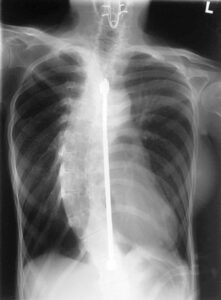

Comunicato Stampa Presso L’Ospedale I.R.C.C.S. “Casa del Sollievo della Sofferenza” di San Giovanni Rotondo, centro d’eccellenza nella chirurgia vertebrale per...